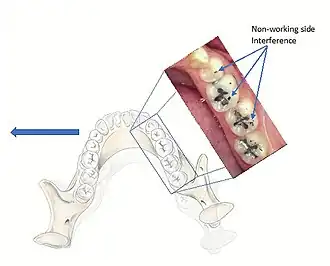

An occlusal interference is any tooth contact that prevents, or hinders harmonious mandibular movement (an undesirable tooth contact).[12]

The occlusal interferences may be classified as follows:[22]

- Working Side Interference: When there is a heavy or early tooth contact between the maxillary and mandibular teeth on the side that the mandible is moving towards, and this contact may or may not discludes the anteriors.[18]

- Non-Working Side Interference: An occlusal contact on the side the mandible is moving away from that prevents harmonious movement of the mandible. These have the potential to be more destructive in comparison to WS interferences due to the obliquely directed forces.[23]

- Protrusive Interference: Contacts that occur between the distal aspects of the maxillary posterior teeth and the mesial aspect of the mandibular posterior teeth. These interferences are potentially very damaging and may even cause an inability to incise properly due to the close proximity of the interference to the muscle.

When the dentist is providing restorations, it is important that these do not create an interference, otherwise the restoration will receive increased loading. As for deflective contacts, interferences may also be associated with parafunction such as bruxism (although evidence is weak) and may adversely affect the distribution of heavy occlusal forces. Interferences may also cause pain in the masticatory muscles due to altering their activity,[24] however there is large controversy and debate as to whether there is a relationship between occlusion and temporomandibular disorders. Almost all dentate individuals have occlusal interferences, and therefore they are not seen to be an etiology of all TMDs. When there is an acute change or significant instability in the occlusal condition and subsequently represents an etiological factor for a TMD, occlusal treatment is required.